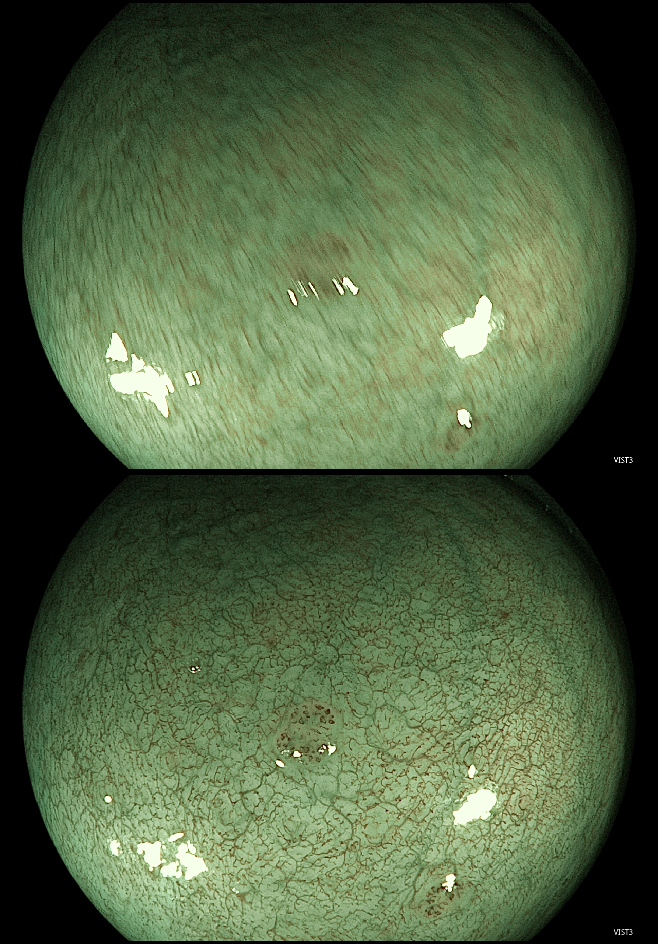

智能预冻结技术(i-PreFreeze):临床内镜检查中,镜体的轻微晃动便能导致图像冻结功能难以捕捉清晰影像。在使用光学放大内镜在放大模式下观察时,由于成像视野小,该现象尤为显著。

iEndo智能预冻结技术通过分析冻结前后的多帧图像,自动选取最佳图像进行展示,即使在动态检查过程中也能获取高质量图像,显著提高早癌筛查的效率和准确性。

▲常规冻结(上)与智能预冻结(下)AI辅助质控与诊断:目前在上、下消化道检查时,iEndo均可使用开立自研内镜AI功能,辅助内镜医生进行临床诊断。比如,用于上消化道检查的AI胃部质控功能,使用时屏幕会实时显示模拟的胃部三维渲染图像,显示当前检查部位、已检部位以及未检部位,并以不同颜色标记,以便医者实时了解检查进度。